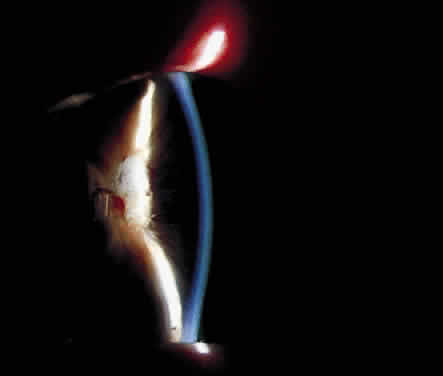

BAND KERATOPATHY

Long-standing chronic iridocyclitis, especially in children, may result in calcific band keratopathy, the deposition of calcium hydroxyapatite in the cornea at the level of Bowman's membrane. Band keratopathy usually begins as grayish-white opacities at the periphery of the interpalpebral region. The opacification may spread centrally and in time may form a complete band within the interpalpebral zone. A lucid interval is noted between the band and the limbus because Bowman's layer does not extend to the absolute limbus.6 Small clear areas are noted in the opacity, representing the location where corneal nerves penetrate Bowman's layer. These holes impart a “Swiss cheese” appearance to band keratopathy (Fig. 1). Band keratopathy should be distinguished from Vogt's limbal girdle and spheroidal degeneration. Occasionally, band keratopathy is atypical and starts centrally. Rarely, it forms a reticular pattern resembling lattice dystrophy called superficial reticular degeneration of Koby.7